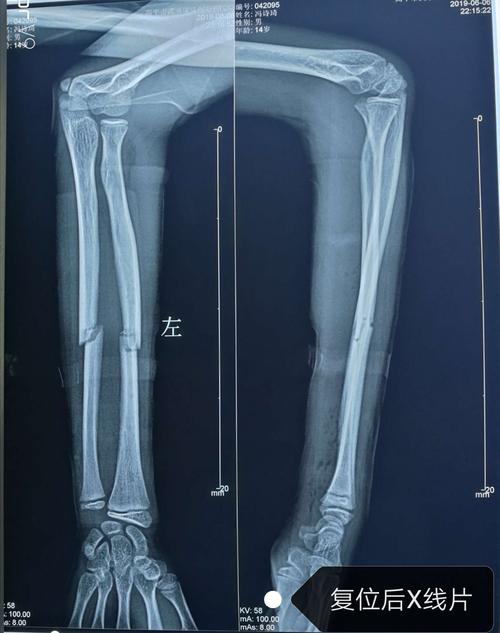

拍摄的吴菊萍受伤左臂的x光片,医生诊断为手臂左尺桡骨多段粉碎性骨折

尺桡骨中段骨折